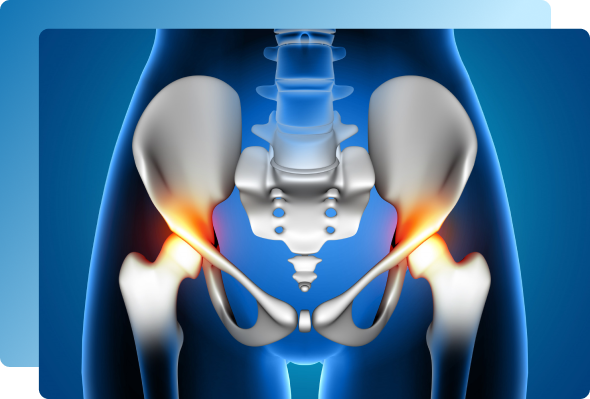

The sacroiliac joints sit on either side of the spine, connecting the sacrum

(the base of your spine) to the iliac bones of your pelvis.

These joints play a vital role in:

Transferring weight between the upper body and legs

Providing stability during walking or standing

Absorbing shock from movement

When irritated or inflamed, they can produce deep, localized pain that may radiate to the buttock or thigh.

Because SI joint pain can mimic other spine or hip problems, accurate diagnosis requires

a combination of clinical assessment and image-guided testing

Special tests that stress the SI joint (e.g., FABER, Gaenslen, or compression tests) reproduce pain when the joint is inflamed.

X-rays or MRI: reveal inflammation, arthritis, or joint changes.

CT Scan: may show bone irregularities or ankylosis in chronic cases.

An image-guided SI joint injection with numbing medication remains the gold standard for confirming the diagnosis—if the pain temporarily disappears, the joint is the source.